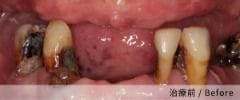

實際案例分享

案例一